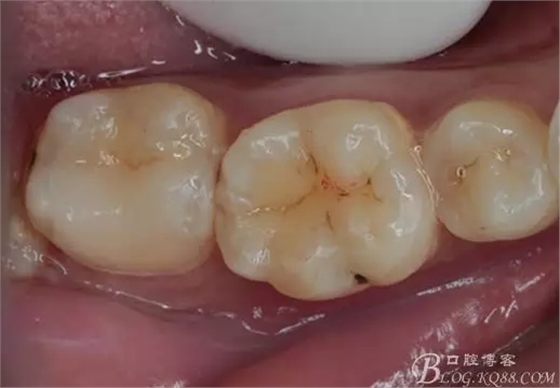

一周后復(fù)診,37臨時(shí)充填物完好。去除臨時(shí)充填物,清潔基牙,試戴嵌體,就位良好,邊緣密合。取下嵌體,常規(guī)處理,9.5%HF處理20S,沖洗一分鐘,95%酒精蕩洗5分鐘?;劳磕?7%的磷酸凝膠,釉質(zhì)區(qū)域酸蝕30S,本質(zhì)區(qū)域15S。粘固用的是3M第八代粘接劑套裝,照說明書逐步操作。最終固化時(shí)涂滿阻氧劑,每個(gè)牙面最少光照30S,光固化燈用漸強(qiáng)模式。常規(guī)調(diào)合,配合硅膠尖套裝拋光。術(shù)后常規(guī)醫(yī)囑,不適隨診。

回訪:術(shù)后一周電話回訪無異常。